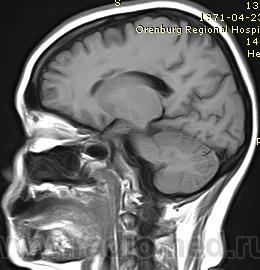

МРТ головного мозга, мозолистое тело

Женщина, около 40 лет. Заболела остро несколько месяцев назад, по КТ было выставлено субарахноидальное кровоизлияние. Снимки, как обычно, остались домаangry.

В настоящее время невролога насторожили признаки поражения мозолистого тела - апраксия. Для исключения опухоли мозолистого тела направлена на МРТ.

Я думаю инфаркты в мозолистом теле.

Да так и есть! У меня возникла мысль о Маркиафава-Беньями. Но никакого анамнеза. Женщина довольно молодая, сохранная, социально адаптирована. Потом выяснилось, что КТ делали в начале заболевания дважды с интервалом в несколько дней. Первый раз написали субарахноидальное кровоизлияние, второй раз внутрижелудочковое кровоизлияние в стадии рассасывания. Это меня озадачило. Я потребовала снимки, и получила их. Что скажете?

Снимки мелковаты, но кажется видно, что это свежий инфаркт в мозолистом теле. Кровоизлияний нет. При обследовании у больной выявили наследственную тромбофилию.

Я впервые встретилась с такой локализацией инфаркта. Если у кого-нибудь есть подобные наблюдения, может поделитесь. Было бы интересно узнать насколько часто они встречаются.

да, мозолистое и выше пострадавшее, на Т2 видно

Мало снимков и очень плохо видно. Но здесь отмечается небольшая дефармация боковых желудочков, кистозные участки в мозолистом теле, возможно, с учетом предыдущий исследований и расценивать нужно, как постишемические изменения.

Именно так я и расценила: инфаркт в мозолистом теле. На КТ острый инфаркт - отек и понижение плотности мозолистого тела, на МРТ последствия инфаркта.

Острый инфаркт зафиксирован на КТ+анамнез, острое начало заболевания.

На МРТ через несколько месяцев постинфарктные изменения с признаками геморрагической трансформации в зоне некроза.

Мне не очень верится в то, что почти все мозолистое тело, за исключением валика, сразу подверглось инфаркту. Для этого нужна симметричная окклюзия обеих перикаллезных артерий. Откуда она взялась, особенно учитывая отсутствие "цисциркуляторного" анамнеза?

Я бы все-таки поставил на первое место болезнь Мархиафавы-Биньями. Вот, нашел статью про разные поражения мозолистого тела: http://www.ajronline.org/content/179/1/251.full. Выдрал оттуда картинку, на ней хроническая стадия болезни. Видно то же самое: атрофия клюва и ствола мозолистого тела, валик сохранен.

Насчет Маркиафавы, первая мысль была о нем. Но алкогольного анамнеза нет. Не помню писала я или нет, у больной при обследовании выявили наследственную тробофилию.